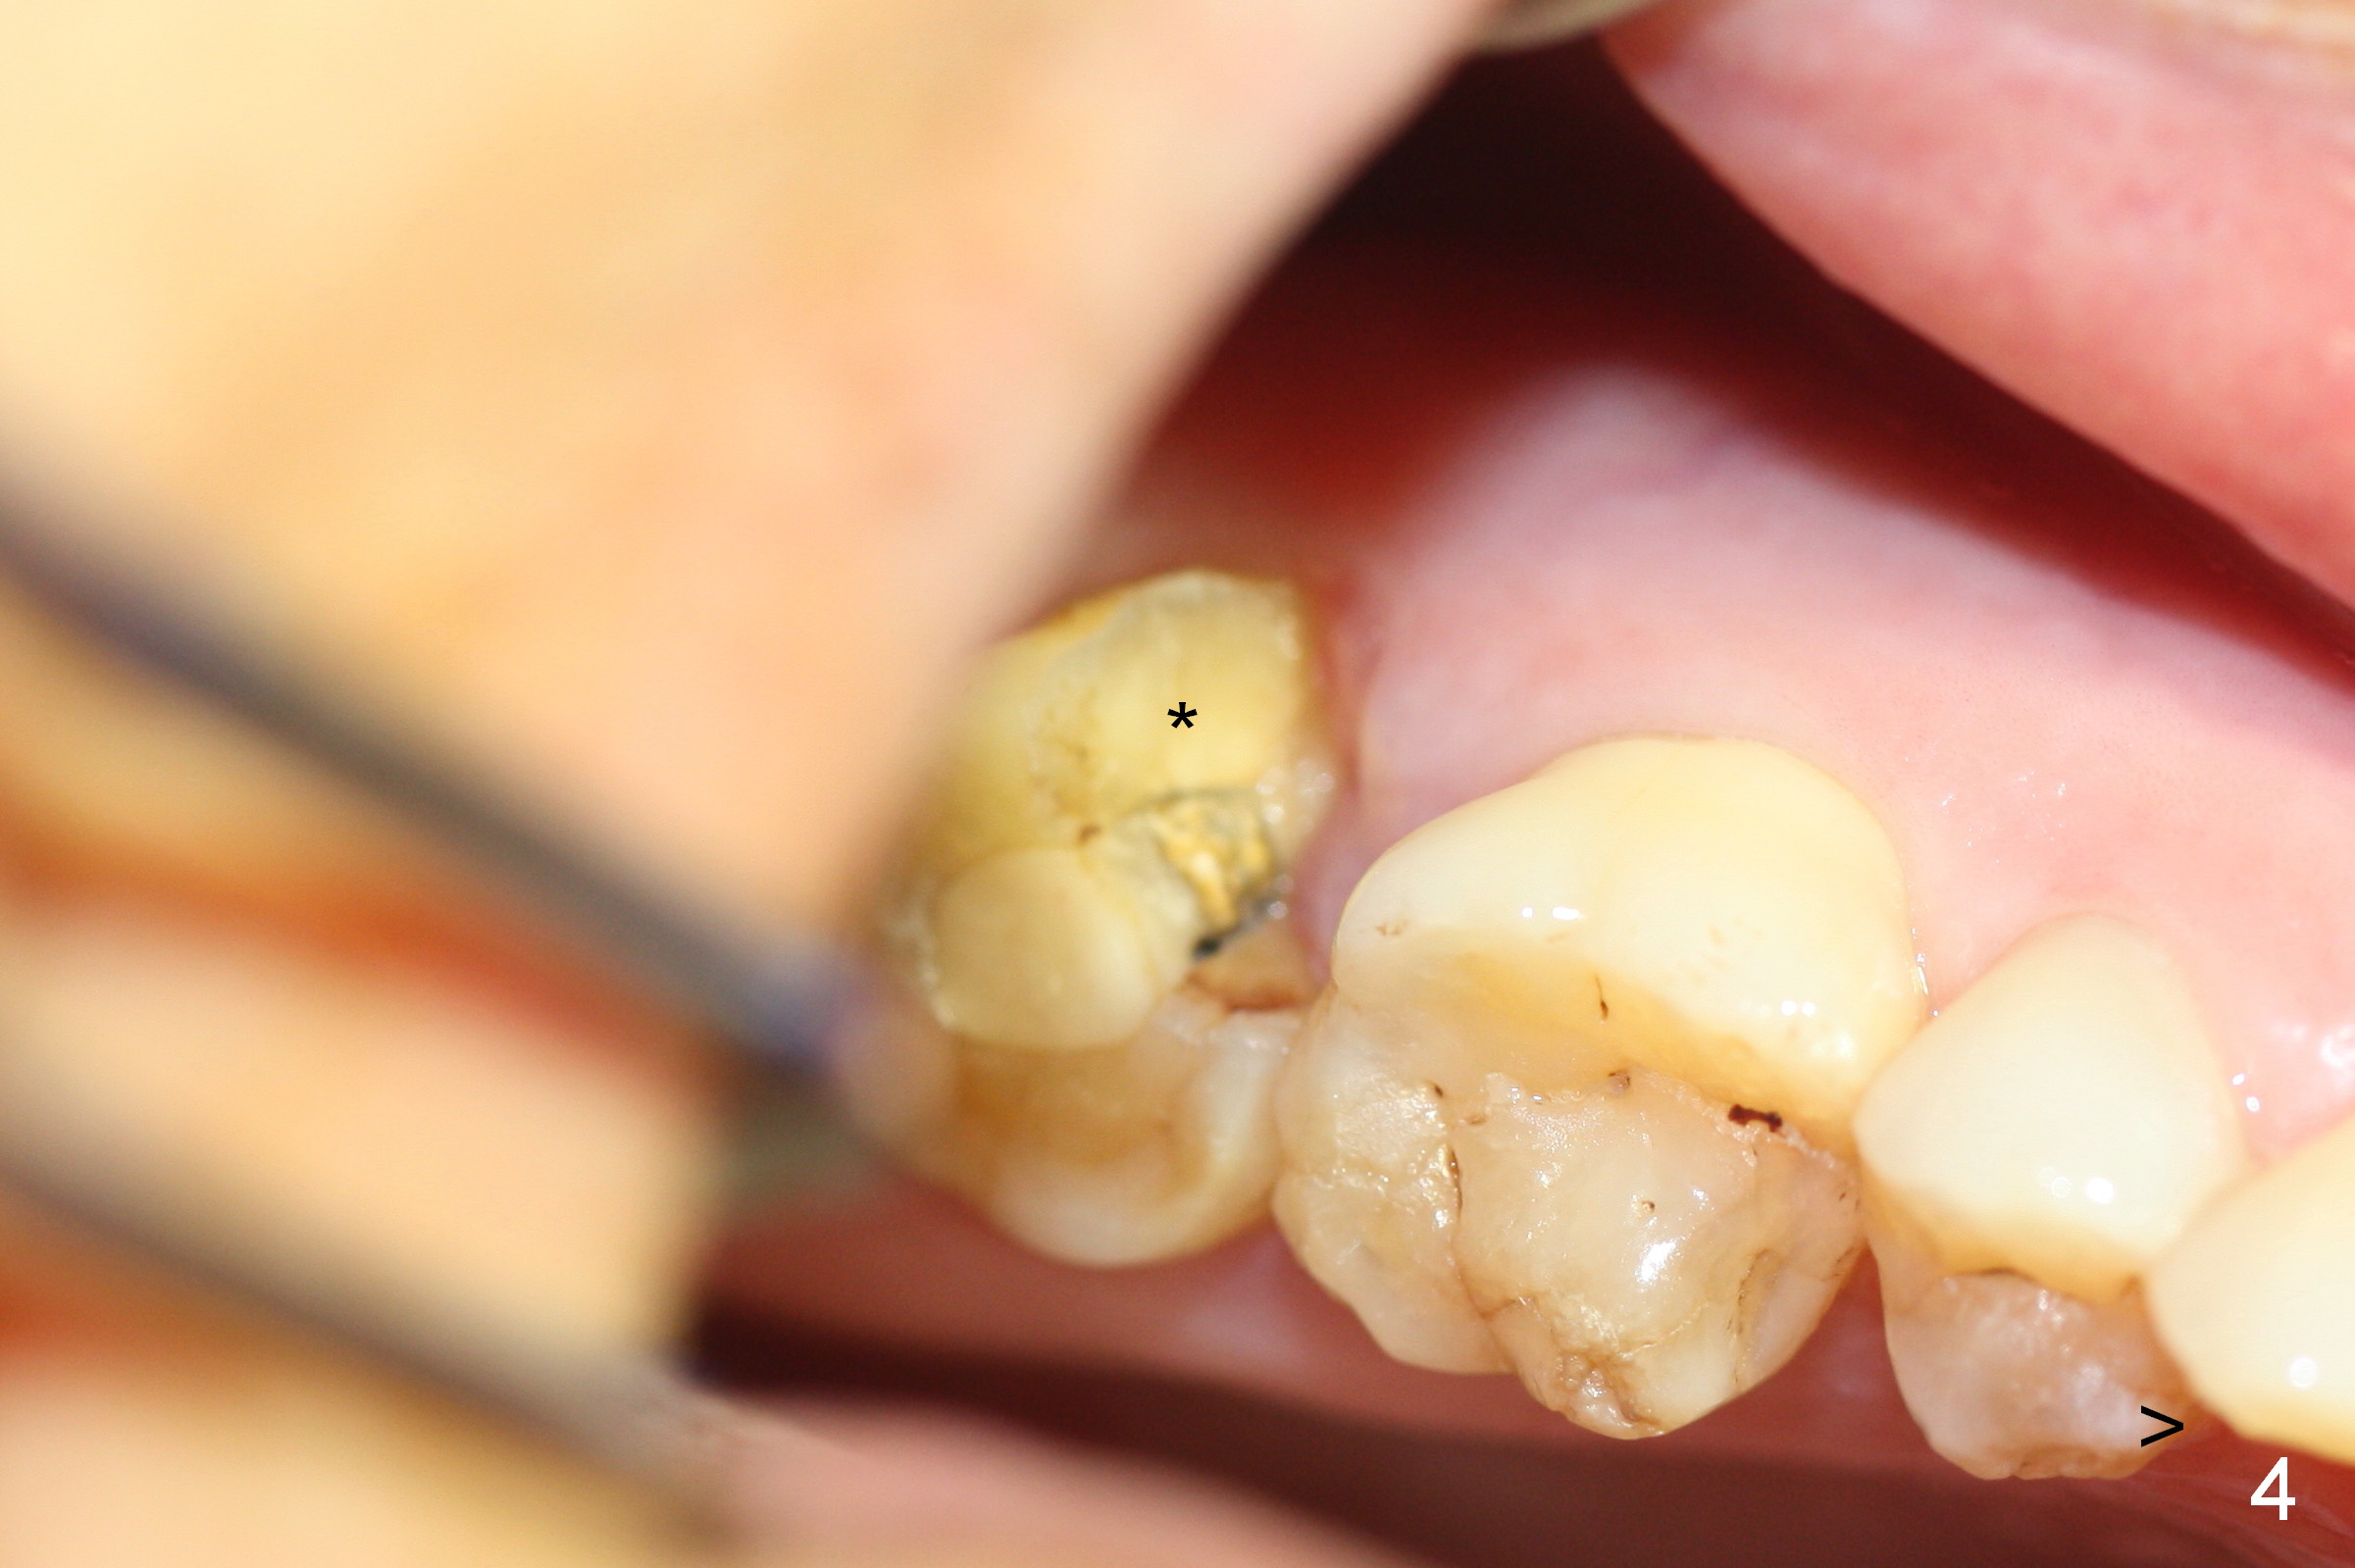

A 65-year-old lady is at early stage of Parkinson's disease and appears to be a bruxer. There are multiple chipped teeth, including #2 (Fig.1,4 *). She chooses implant over RCT retreat. A tissue-level implant (Fig.2) matches the root shape of the affected tooth better than a bone-level one (Fig.3), because of taper. The buccopalatal and mesiodistal dimensions of the extraction socket are 11 and 8 mm, respectively (Fig.5,7).

The buccal roots are fused. The buccal socket (BS) seems to be larger than the palatal one (PS). There is a septum (S) between the 2 sockets. Both the buccal and palatal plates (BP, PP) are intact. The anatomy is illustrated in Fig.6a (buccopalatal section) with the same abbreviations, mentioned above. SF: sinus floor.

Probably due to bruxism, there is limited vertical restorative space. The margin is subgingival except buccal (Fig.10,11). An immediate provisional (Fig.12 P) appears to have to be fabricated to prevent soft tissue from covering the margin during osteointegration. It is our intention to make gingival envelop larger than the definitive crown cervix. It would be easier to remove a permanent cement later on for peri-implantitis prevention.